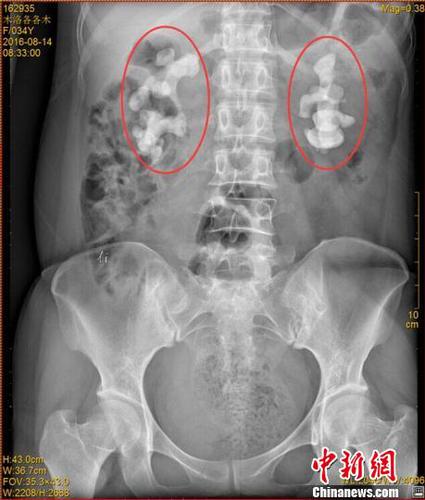

各各木术前影像图片,红圈内为巨大肾结石?!≈有馈∩?/div>

中新网成都11月7日电 (王鹏)记者7日从四川省结石病医院获悉,该医院近日收治了一名罕见肾结石病人。来自四川凉山的34岁女子各各木,双肾长出10厘米巨型结石,肾内空间几乎全被结石填满。

记者了解到,由于各各木肾脏内部几乎全被结石填满,常规的开放式手术并不适用。医院目前已对其进行了4次难度颇高的微创手术,且在进一步观察治疗当中。